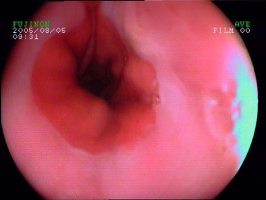

为了能够切实提高食管炎的临床诊断水平,北京德胜门中医院率先引进高新胃镜设备——奥林巴斯无痛电子胃镜,解决了传统胃镜检查痛苦的问题。

一、清晰直观:高清晰度、高分辨率,尤其是一些微小病变甚至粘膜层的病变,均可明确诊断。

二、没有痛苦:采用超细纤维软管,安全且微创,悬空进入,对食道、胃肠道粘膜不会造成损伤,能清晰的检查病变情况。

三、诊断率高:放大图像,可细微观察直达毛细血管的病变,有效避免误诊、漏诊,内镜下还可进行取样活检,因此诊断率较高。